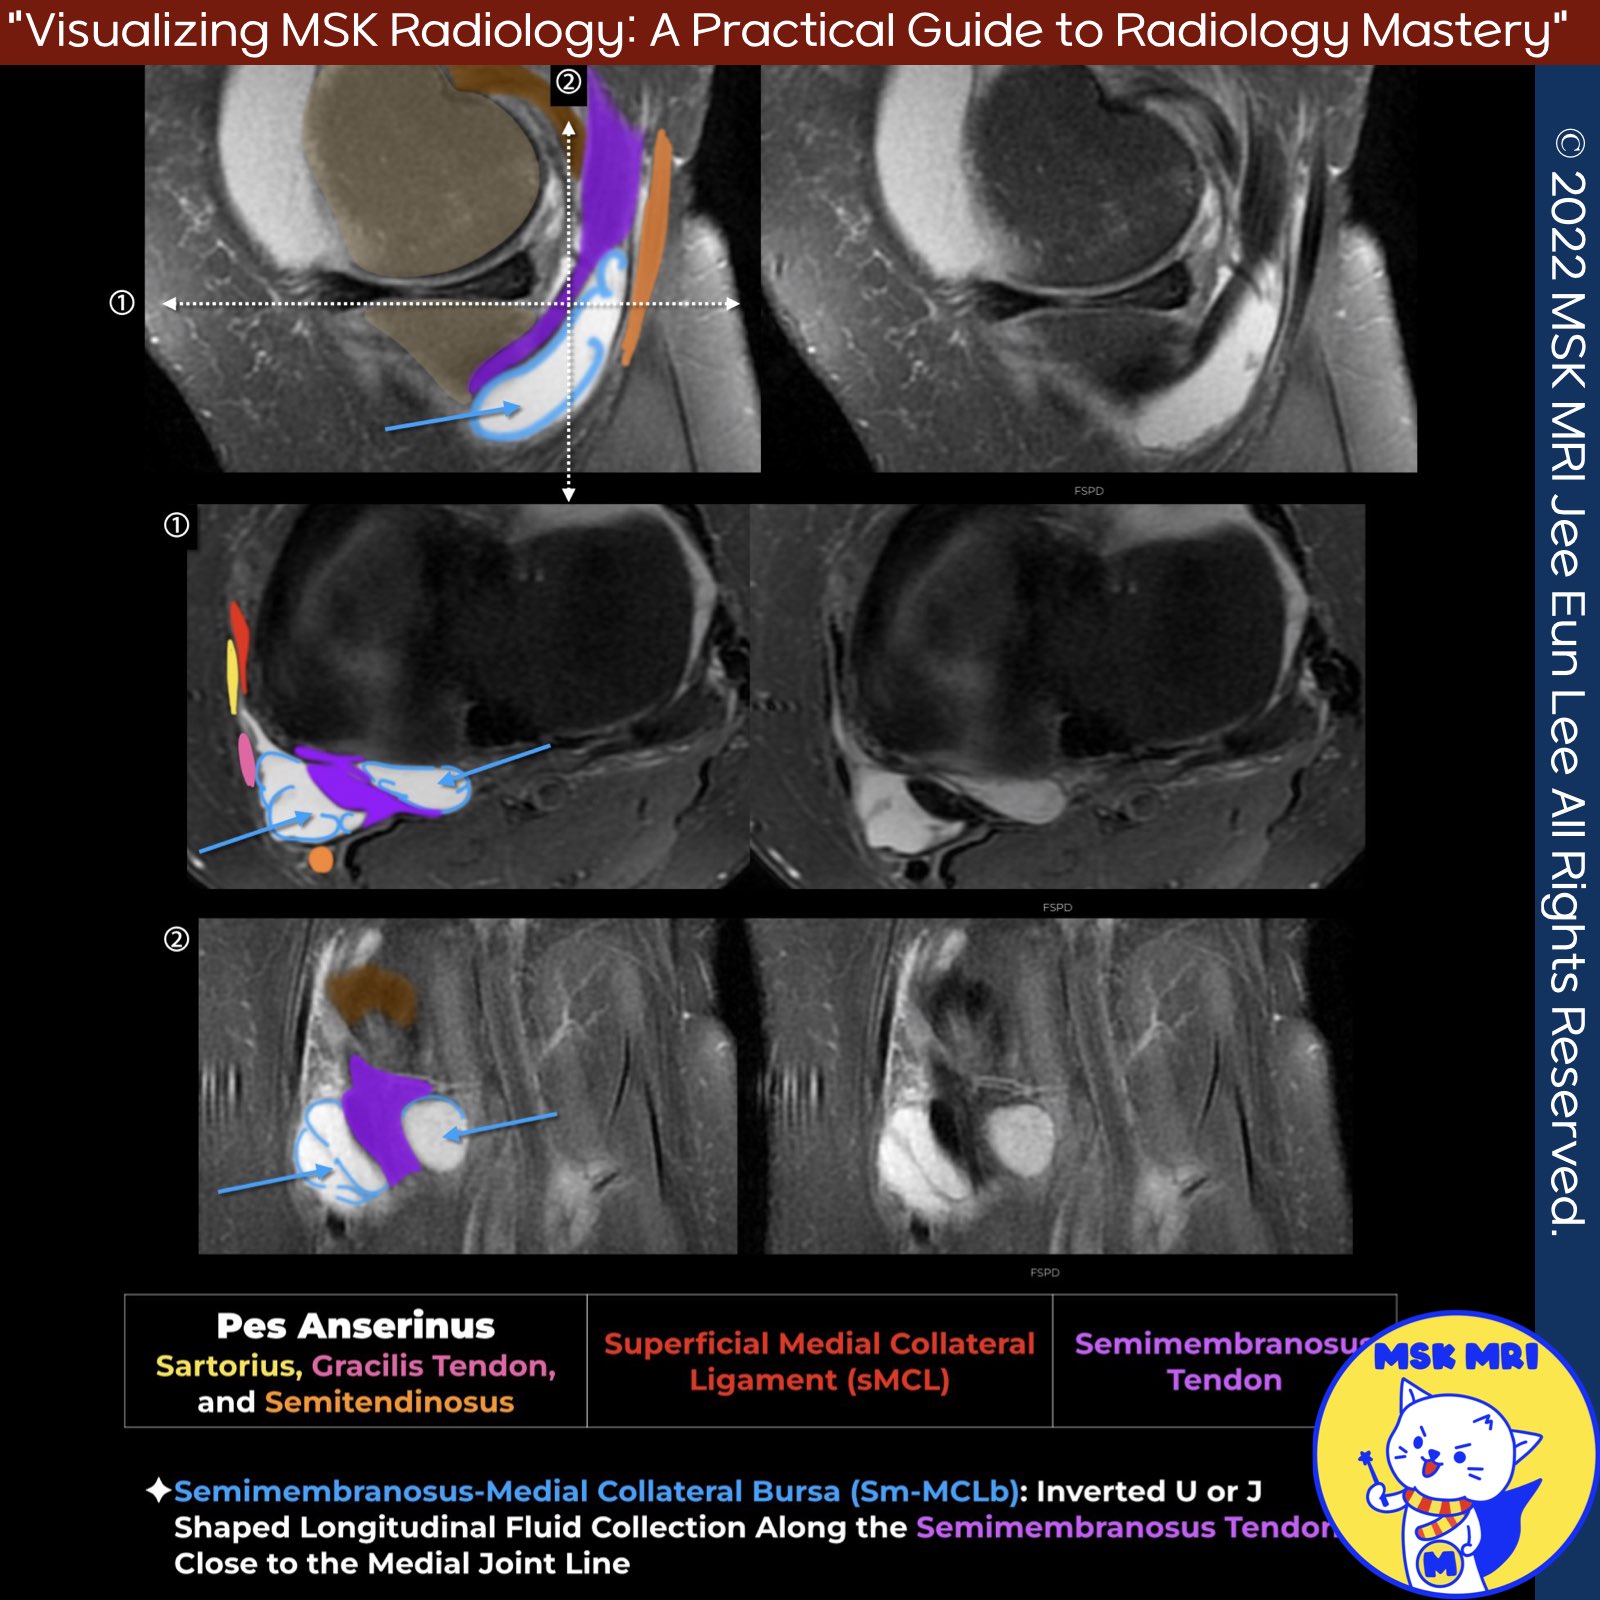

📌Semimembranosus Bursa:

- Horseshoe-shaped synovial bursa around the semimembranosus tendon near posteromedial tibial rim

- Inflamed/distended bursa presents as a synovial-lined space wrapping the tendon

- Demonstrates characteristic reverse 'J' shape or 'inverted-U' shape on imaging

✅Direct Arm of Semimembranosus Tendon

- Principal attachment of the semimembranosus tendon

- Attaches to posteromedial aspect of tibia, just distal to the joint line

- Forms a C-shaped 5-mm-thick band with the anterior arm

✅Anterior Arm of Semimembranosus Tendon

- Seen on peripheral medial sagittal images, curving anteriorly

- Appears as a round hypointense structure on coronal images, adjacent to medial tibia, passing under the MCL